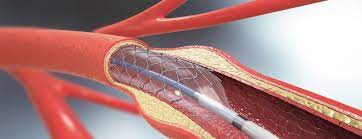

Overview

Package includes:

Days in hospital : 3 to 4 Days (For patient and one attendant)

Days in hotel : 7 Days (For patient and one attendant)

Room type in hospital : Shared

Room type in hotel : Private

Hotel category: Standard

Value added benefits of the Coronary Angioplasty:

Overview

Package includes:

Days in hospital : 3 to 4 Days (For patient and one attendant)

Days in hotel : 7 Days (For patient and one attendant)

Room type in hospital : Shared

Room type in hotel : Private

Hotel category: Standard

Value added benefits of the Angioplasty PTCA :

Overview

Package includes:

Days in hospital : 4 to 5 Days (For patient and one attendant)

Days in hotel : 7 Days (For patient and one attendant)

Room type in hospital : Shared

Room type in hotel : Private

Hotel category: Standard

Value added benefits of the Renal Angioplasty:

Overview

Package includes:

Days in hospital : 4 to 5 Days (For patient and one attendant)

Days in hotel : 8 Days (For patient and one attendant)

Room type in hospital : Shared

Room type in hotel : Private

Hotel category: Standard

Value added benefits of the Vertebral Angioplasty:

Overview

Package includes:

Days in hospital : 2 to 3 Days (For patient and one attendant)

Days in hotel : 14 Days (For patient and one attendant)

Room type in hospital : Shared

Room type in hotel : Private

Hotel category: Standard

Value added benefits of the Percutaneous transluminal coronary angioplasty (PTCA):